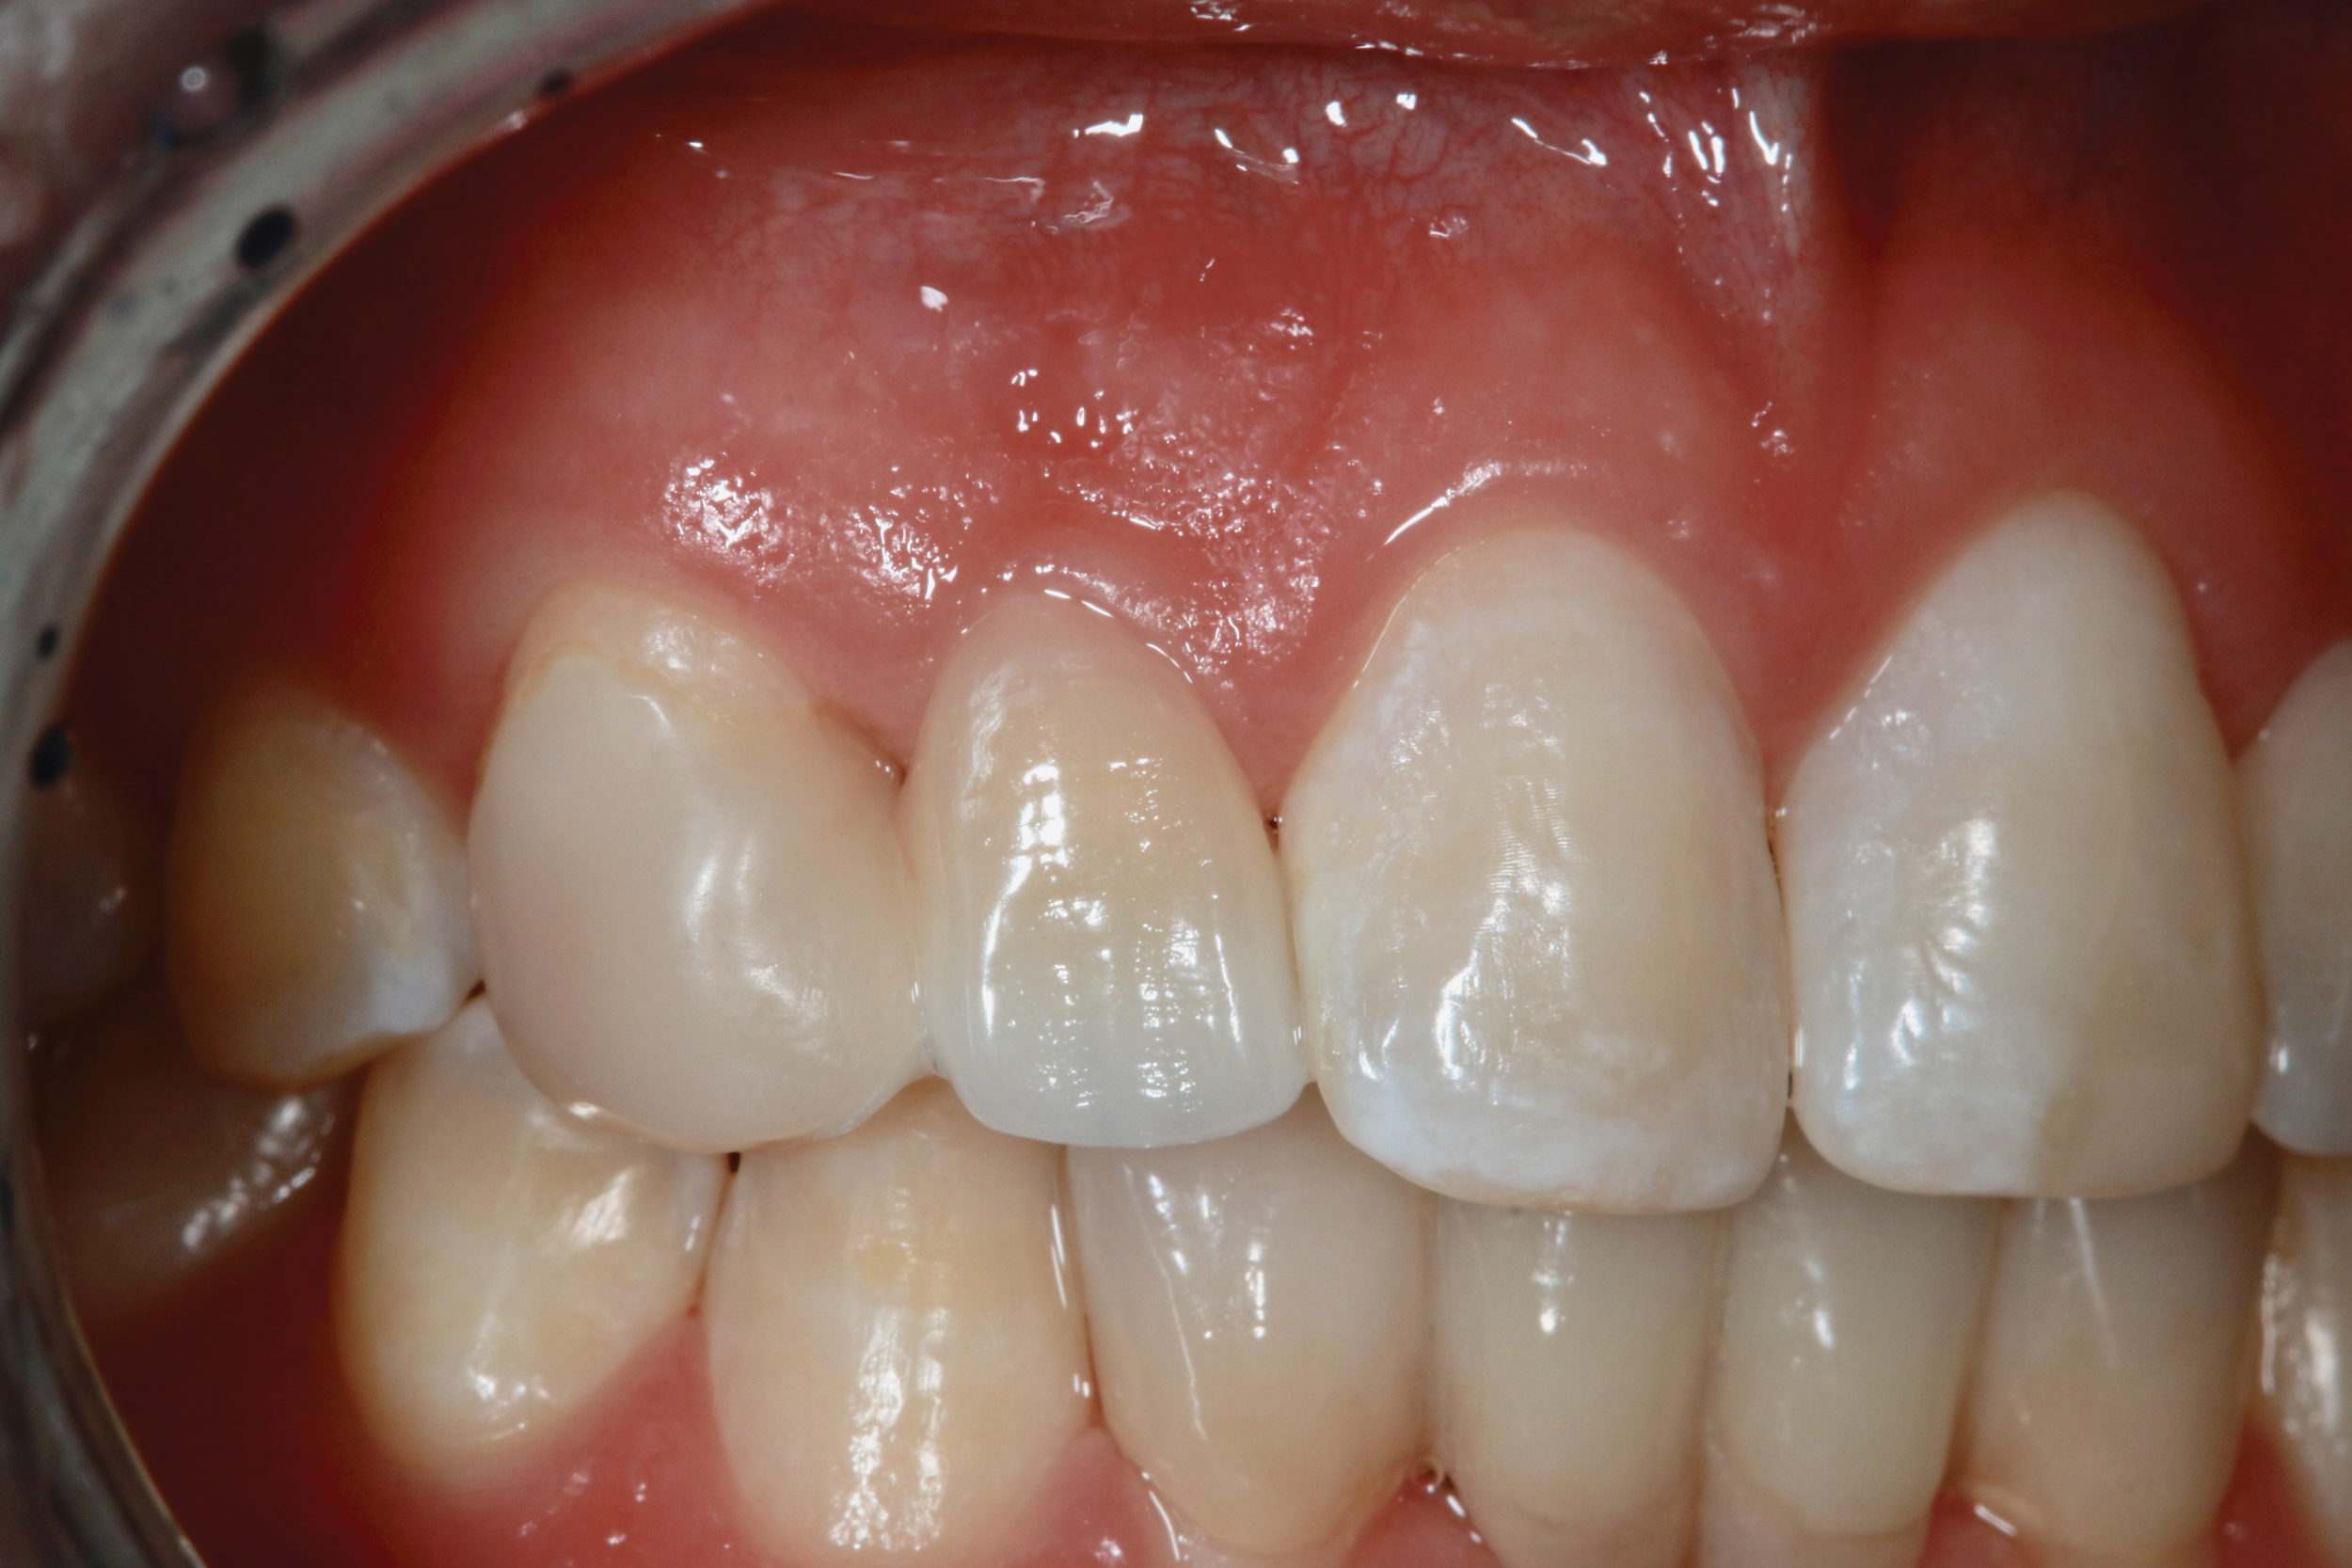

Fig 15. Four-year postoperative photograph of zirconia bonded bridge replacing tooth No. 7.

Figure 15

Fig 16. Occlusal view of the zirconia bonded bridge in Fig 15 at 4-year postoperative showing one wing on the canine abutment and a small anti-rotation extension from the pontic onto the distolingual surface of tooth No. 8.

Figure 16

There are a number of requirements to achieve a successful bonded bridge. First, the edentulous site must be approximately the same width as the contralateral tooth. There also must be adequate soft tissue to provide esthetic emergence contours for the ovate pontic. Some clinicians may be concerned that the ovate pontic will not adequately maintain the soft tissue and, over time, the tissue will shrink away from the pontic. However, the soft tissue under an ovate pontic has been shown to be quite stable long-term.39 An example of this is shown in Figure 15.

Additionally, to accomplish a bonded bridge, the abutment tooth must be large enough to provide 30 mm2 of enamel surface and a 3 mm connector height.40 The zirconia wing must be at least 0.7 mm thick to provide the required strength.40 Ideally, this space is created orthodontically to ensure there will be minimal reduction of the lingual enamel. For long-term success, the abutment must be bonded to an enamel substrate.

Next, the pontic must have resistance to facial displacement. This is accomplished by adding a slight extension on the pontic adjacent to an unbonded tooth; this will prevent the pontic from moving facially when loaded from the lingual (Figure 16). There should be no preparation on the unbonded tooth, nor should the extension be bonded so flossing may be easily accomplished. There must also be resistance form on the abutment, which can be best achieved with a vertical groove or box on the lateral surface of the abutment, adjacent to the edentulous site (Figure 17).29 There should be no excursive contacts on the pontic. Lastly, an evidence-based bonding protocol is essential for long-term success.